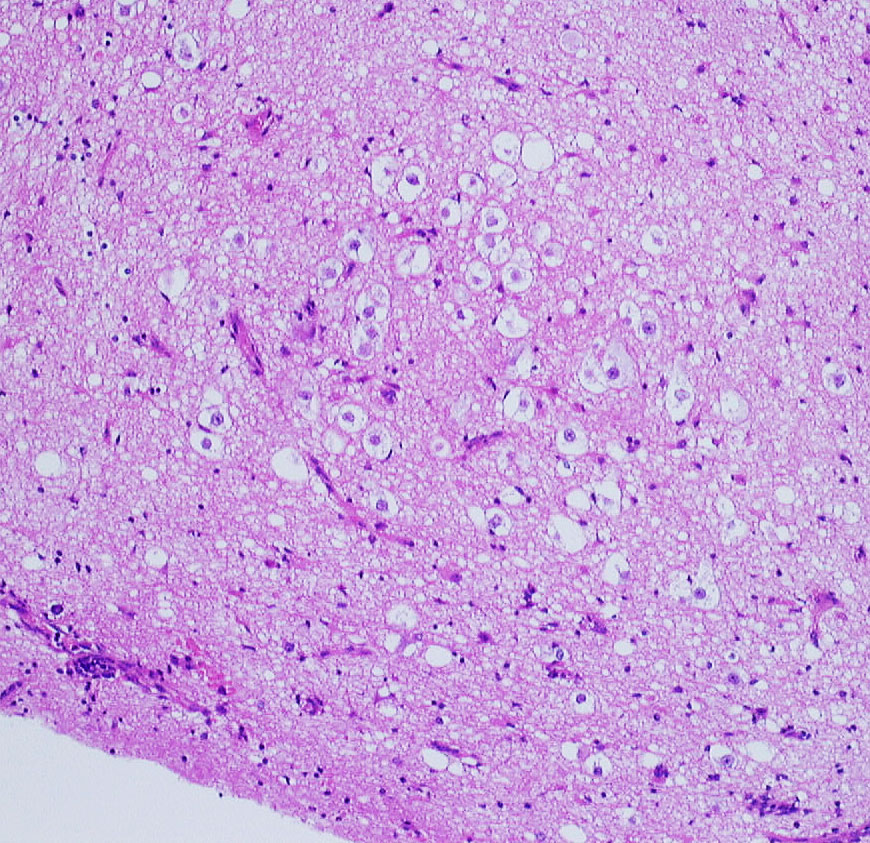

小児の神経節細胞腫 gangliocytoma グレード1(過誤腫のような良性腫瘍)

大脳皮質に大型の核を有する円形の神経細胞が散在しています。神経細胞間にグリア細胞がありますが腫瘍性増殖を示しません。MIB-1は1%以下でした。血管周囲にリンパ球浸潤があります。